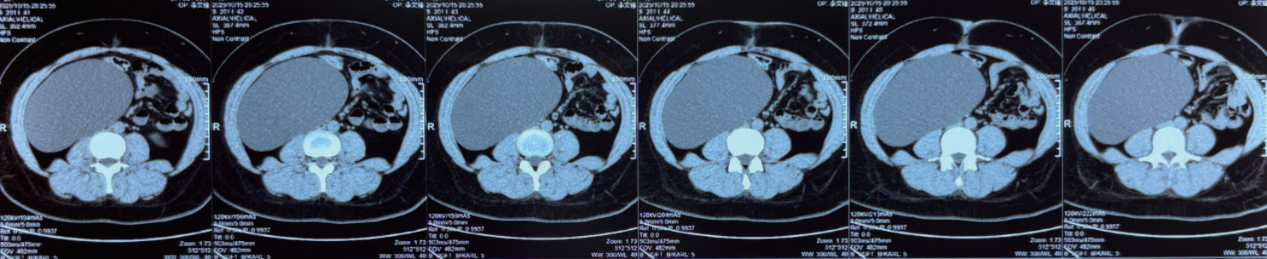

手术在医院船手术室进行,手术当日张高峰医生协助完成全身麻醉,张涛医生上台协助完成手术。术中探查发现:巨大囊性肿瘤来自升结肠外腹膜后间隙,大小约18 cm×10 cm,上缘达肝脏下缘,下缘至右髂窝,将升结肠、回肠、右侧输尿管及卵巢动静脉推挤至左侧腹腔。手术团队选择腹膜后入路,利用超声刀将肿瘤表面腹膜打开,将肿瘤与周围肠管、血管、输尿管等器官依次游离,仔细止血,最终完整切除肿瘤(图2)。

image.png

图2 术后腹部CT